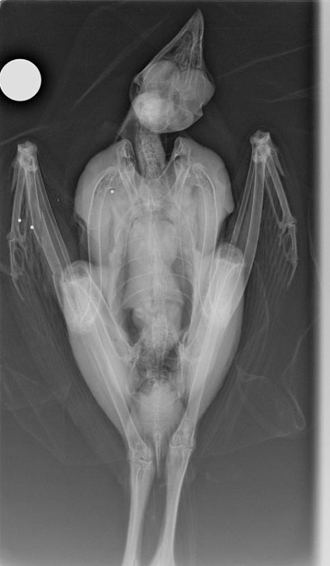

Ακτινογραφία του πυροβολημένου γερακιού,

όπου είναι εμφανή τα σκάγια στο στέρνο

και την αριστερή φτερούγα.

Το αγέρωχο αρπακτικό βρέθηκε στα τέλη Οκτωβρίου τραυματισμένο στη φτερούγα σε δασική περιοχή του Σμόλικα από κατοίκους του χωριού Αγία Παρασκευή (Κεράσοβο) και οι υπάλληλοι του Δασαρχείου Κόνιτσας που ειδοποιήθηκαν κινητοποιήθηκαν αστραπιαία έτσι ώστε ο πολύτιμος κυνηγός να μεταφερθεί τάχιστα στο Κέντρο Περίθαλψης ΑΝΙΜΑ στην Αθήνα όπου οι ακτινογραφίες έδειξαν ότι είχε πυροβοληθεί με ψιλά σκάγια από κυνηγετικό όπλο τα οποία είχαν προκαλέσει κάταγμα στην φτερούγα του. Μετά την επιτυχή αποκατάσταση του κατάγματος ακολούθησε περίοδος αποθεραπείας η οποία περιέλαβε εντατική εκγύμναση από εξειδικευμένους συνεργάτες της ΑΝΙΜΑ.